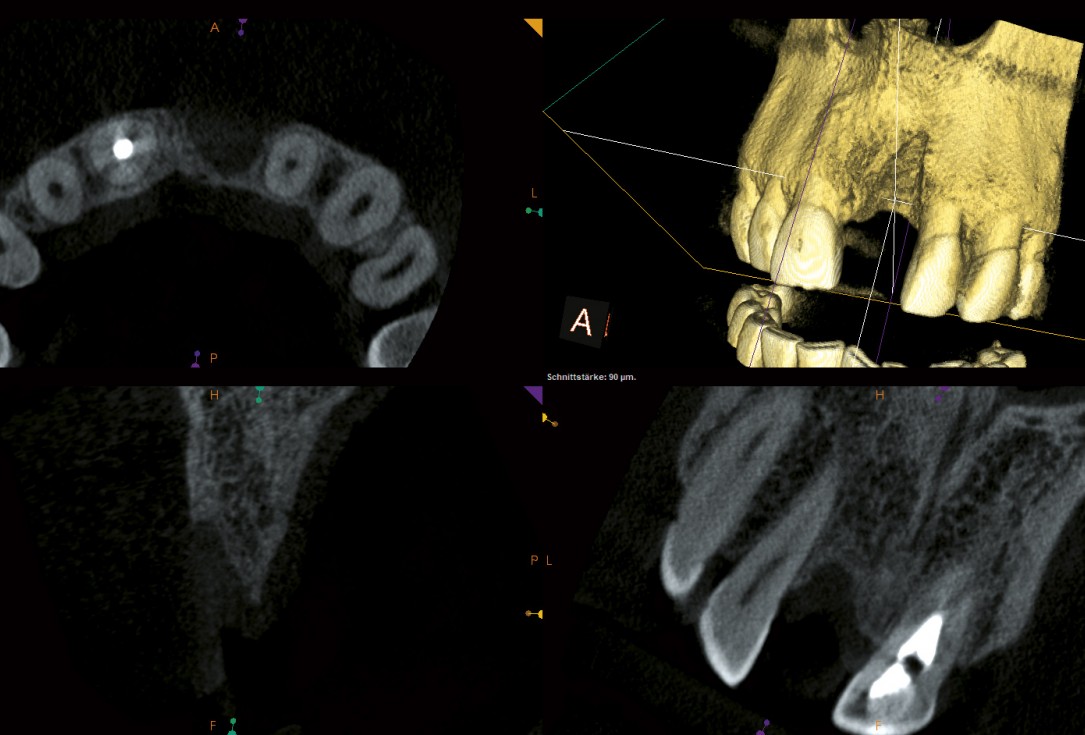

04/18 - CBCT scan after tooth extraction

Block augmentation with maxgraft® and cerabone® – PD Dr. Dr. F. Kloss